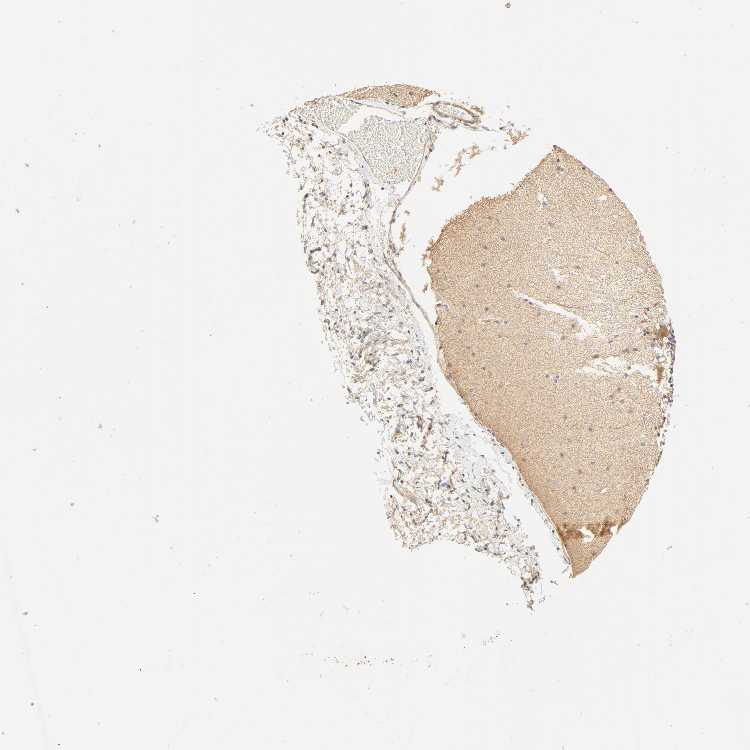

CEREBELLUM - Antibody stainingi

Antibody staining in the annotated cell types in the current human tissue is reported as not detected, low, medium, or high, based on conventional immunohistochemistry profiling in selected tissues. This score is based on the combination of the staining intensity and fraction of stained cells.

Each image is clickable and will lead to virtual microscopy that enables deeper exploration of all samples and also displays staining intensity scores, fraction scores and subcellular localization as well as patient and tissue information for each sample.

Antibody HPA004714

Purkinje cells Medium

Cells in granular layer Low

Cells in molecular layer Medium